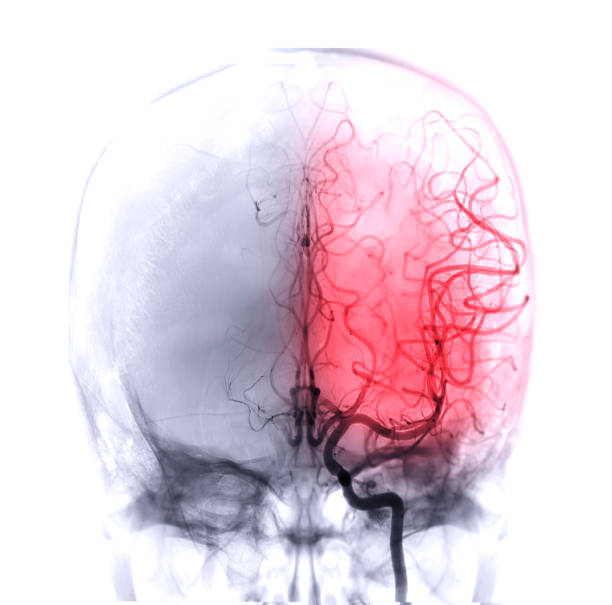

뇌졸중 증상

모야모야병의 가장 일반적인 증상 중 하나입니다. 뇌졸중 증상은 언어 장애, 인지 장애(기억력 감퇴, 학습 장애 등), 시각 장애(시야 손실, 양안 시력 장애), 운동 장애(양쪽 다리나 팔의 약화, 불균형, 혹은 어색한 움직임 등) 등이 있습니다.

반복성 뇌졸중

모야모야병은 뇌졸중 발생 위험이 높습니다. 반복적인 뇌졸중은 뇌조직 손상, 체력 저하, 기능 손상 등을 초래할 수 있습니다.